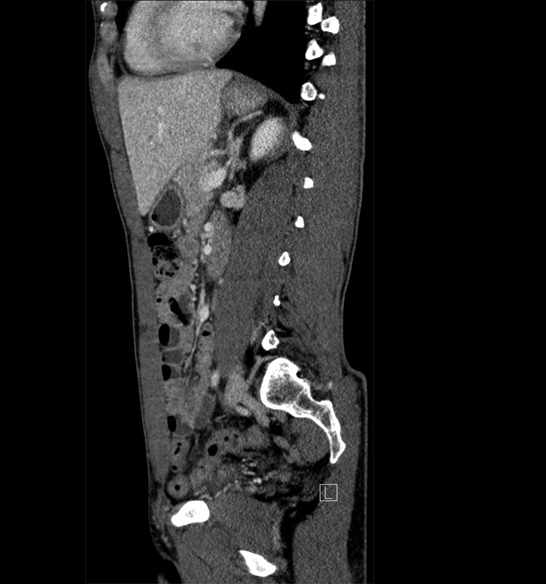

Body

Covers abdominal CT anatomy.